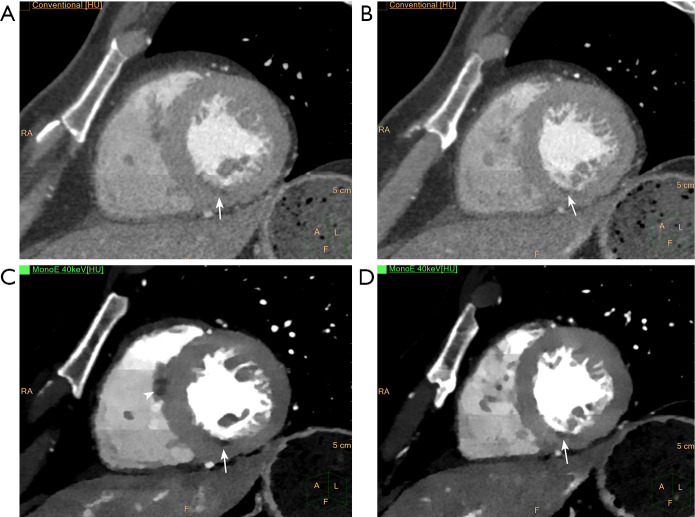

The inherent ability of VMI to reduce beam hardening artifacts in the myocardium, especially near the diaphragm, has been investigated in a series of studies determining the potential advantage of using DECT for CTP. Experimental data using phantoms and animal models showed the technical utility of rsDECT with VMI at energy levels ≥70 keV for reducing beam hardening in myocardial perfusion imaging (68,69). VMI imaging has been shown to decrease beam hardening artifacts especially in the basal inferolateral segment (70). Carrascosa et al. (71) examined the diagnostic performance of stress CTP in patients undergoing both rsDECT with VMI and SECT, using SPECT myocardial perfusion as standard of reference. The area under the curve for detecting segmental perfusion defects was 0.90 (95% CI: 0.86–0.94) for VMI versus 0.80 (95% CI: 0.76–0.84) for SECT (P value =0.0004). Noticeably, the performance continued to be superior even when only segments known to be affected by beam-hardening artifacts were included in the analysis. Use of low-energy VMI (40–70 keV) may provide better discrimination of hypoperfusion segments on rest and stress CTP on rsDECT (72) (Figure 5). Last, VMI can also provide ways of minimizing variability in quantitative myocardial perfusion analysis (68).

Figure 5.

Detection of remote infarcts enhanced by virtual monoenergetic imaging (VMI). Short-axis views through the and base-mid left ventricle (A,B) show very subtle subendocardial hypoattenuation in the inferior left ventricular segments on conventional reconstructions of dual-layer DECT (dlDECT) cardiac angiography (arrows). Use of monoenergetic imaging at 40 keV at the same levels (C,D) helps confirming the remote infarct in this patient with obstructive three-vessel disease (arrows). Also note an unsuspected area of hypoattenuation at the insertion of the right moderator band (C, arrowhead), best noted using VMI.